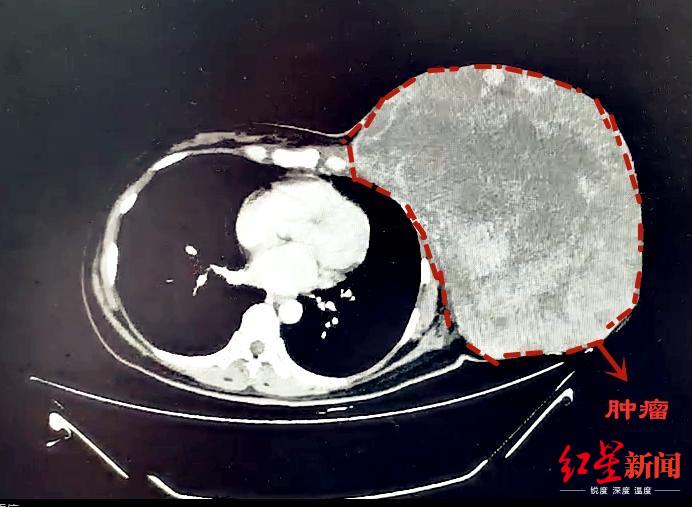

红星新闻从成都市第三人民医院了解到,一颗12斤“巨型”乳腺肿瘤,近日被该院多学科团队顺利摘除。

乳腺肿瘤已成为女性常见的疾病之一。然而,针对47岁的蒋女士来说,她的乳腺肿瘤只能用“心惊胆颤”来形容——直径约30cm、重达12斤!

CT影像

2年多前,蒋女士无意间发现左侧乳腺有一个包块,大约枣子般大小。因为没有疼痛等不适的感觉,她认为“可能问题并不严重”,未进行过系统化的治疗。不过,近半年来她发现包块不仅没有缩小,反而显现出疯长的趋势。发展到现在,包块已经长到“篮球大小”,严重影响了外观,就连走路等生活日常都存在问题。

针对难点和风险,多学科小组进行了充分的准备及并制定应对措施。9月25日,经过4个半小时的手术精细剥离,将近12斤重的巨型肿瘤才被成功完整摘除。后经病理诊断,确定为交界性叶状肿瘤。经过恢复,近日蒋女士顺利出院。